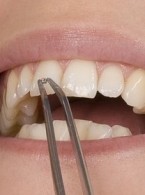

Przemieszczenie fragmentu wypełnienia kompozytowego do dziąsła: rzadkie powikłanie chirurgicznego usunięcia zębów

Zobacz więcej